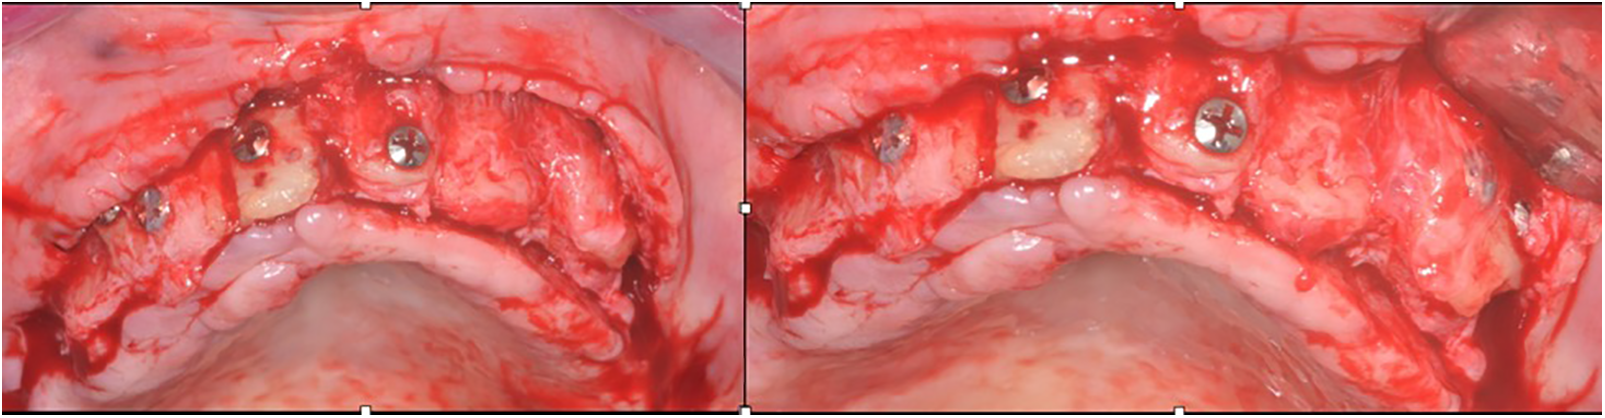

Figure 6: Clinical case 6. The flap reopened, showing the integration

Figure 7: Case 7. Sequential images for the treatment: (A–B) homologous bone graft adjusted and in position, with perforations (decorticalization) to improve the vascularization of the block; (C) occlusal image showing the bone block adaptation on the bedside

The cases were performed following the same sequence, varying the quantity and size of bone used to reconstruct but always keeping the same type of donor region (tibia), e.g., Fig. 1 shows 2 block bone grafts, and Fig. 3 with three blocks. Figs. 1–3 show the procedures done in all of them. Initially, a panoramic X-ray was requested for the primary assessment and overview (Figs. 1 and 2). CBCT was sequentially assessed to verify the necessary dimensions and volume of the bone graft. The surgery was scheduled after receiving the bone graft, and the surgical guide for the implant placement was prepared (Figs. 3 and 8).

The flap was raised according to the needed extension, and the receptor bedside was prepared to receive the homologous bone graft from the tibia. The block graft had an adequate cortical width (≥5 mm), length, height, and medullar area. After adjustments, the homologous bone was fixed using at least 2 screws, transfixing both cortical (buccal and lingual) of the bedside receptor. The immediate osseous volume obtained during the surgery was adequate for posterior rehabilitation (Figs. 1–8); therefore, after the healing period (between 5 and 12 months), a volume loss was expected and found due to tissue remodeling (Fig. 8). After the healing period, the patients were recalled for a new evaluation and panoramic/CBCT analysis (Figs. 1 and 2). Afterward, the surgical procedure for implant placement was scheduled, where the block was trephined to obtain the samples for histological processing (Figs. 1–3 and 8; macroscopic aspects of the histological piece [4 ø mm × 4 mm height]). The implant placement occurred without a significative event, except in one case, in which a small fracture in the block graft was observed (Fig. 2) during the implant installation (after healing); this fact did not harm the procedure and rehabilitation.